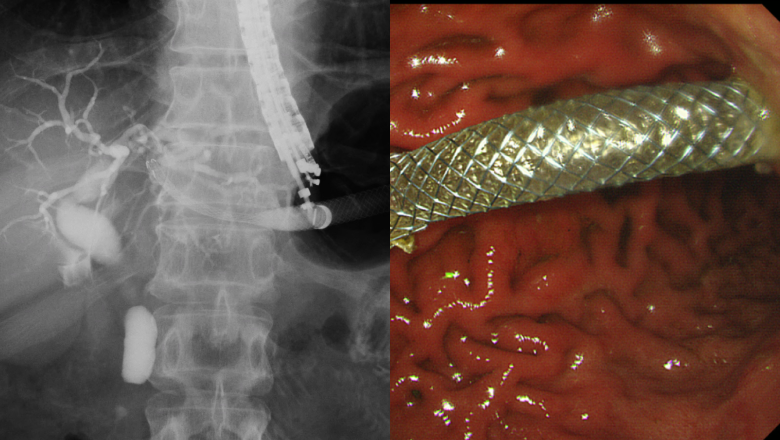

胆膵内視鏡といえばERCPですが、当グループでは、最先端の医療機器を用いた診断・治療を行っています。症例数は、日本有数です。患者さんに、最先端で最良の医療を提供します。

高画質胆道内視鏡による診断